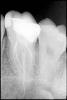

bliss Опубликовано 25 марта, 2010 Поделиться Опубликовано 25 марта, 2010 Здравствуйте. Дайте совет по следующим зубам:1. Шестой справа наверху. Год назад были запломбированы каналы. Недавно стал слегка беспокоить при накусывании. В чем может быть проблема? Надо ли перелечивать каналы? 2. Шестой слева снизу. Лечили года 4 назад. Ни разу не беспокоил, сегодня сказали что надо перелечивать каналы и так оставлять нельзя. 3. Пятый слева наверху (со штифтом). Запломбированы ли там каналы? Что с ним лучше делать: лечить каналы и коронка или что-то еще? Панарамный снимок Шестой справа наверху Ссылка на комментарий

Андрей Опубликовано 26 марта, 2010 Поделиться Опубликовано 26 марта, 2010 Шестой справа наверху, что с ним не так? В нем нужно все каналы перелечивать?В условиях отсутствия каких-либо стандартов качства лечения можно считать, что этот зуб слелан хорошо, у него запломбированы все четыре канала это большая редкость.Однако, если Вы будете делать на этот зуб коронку, я бы Вам рекомендавал перепломбировать каналы, потомучто по моему мнению они недостаточно расширены.Выгледеть картинка должна как-то так.http://content.foto.mail.ru/list/sablinav/fishing/i-104.jpg Ссылка на комментарий

bliss Опубликовано 26 марта, 2010 Автор Поделиться Опубликовано 26 марта, 2010 В условиях отсутствия каких-либо стандартов качства лечения можно считать, что этот зуб слелан хорошо, у него запломбированы все четыре канала это большая редкость.Однако, если Вы будете делать на этот зуб коронку, я бы Вам рекомендавал перепломбировать каналы, потомучто по моему мнению они недостаточно расширены. Действительно, каналы были очень узкие, проходили их с трудом, в два захода, закладывали лекарства для расширения. Может их ширина это все что можно было сделать или каналы можно расширять неограничено (тоесть пока не будет достигнута нужная ширина)? Еще на консультации было сказанно что в самом длинном канале(который по центру) инфекция и возможно обломок инструмента, это действительно там есть? Ссылка на комментарий

Андрей Опубликовано 26 марта, 2010 Поделиться Опубликовано 26 марта, 2010 Действительно, каналы были очень узкие, проходили их с трудом, в два захода, закладывали лекарства для расширения. Может их ширина это все что можно было сделать или каналы можно расширять неограничено (тоесть пока не будет достигнута нужная ширина)? Еще на консультации было сказанно что в самом длинном канале(который по центру) инфекция и возможно обломок инструмента, это действительно там есть?Безгранично расширять не стоит, а до определенного газмера необходимо. Обломков я не вижу. Ссылка на комментарий